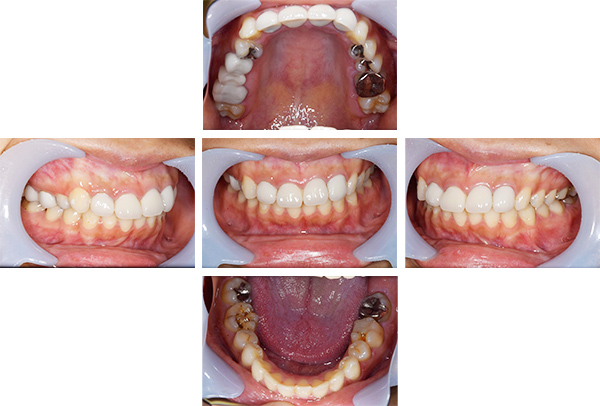

インレー・クラウン・ホワイトニング症例

治療前

治療後

治療期間 11回(4ヶ月)

費用 ・ハイブリッドインレー7本

・ジルコニアクラウン2本

・ホワイトニング:5回

合計:430,500円

治療リスク・副作用 ・詰め物、被せ物をする時は自分の歯を削ることになります

・歯ぎしり・食いしばりが強い方は、セラミックが割れてしまうことがあります。